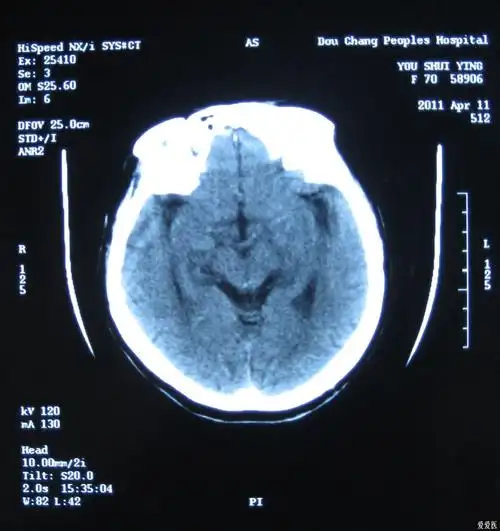

对光反射消失,即予甘露醇250ml静滴,后出现双瞳孔散大,复查头颅ct示